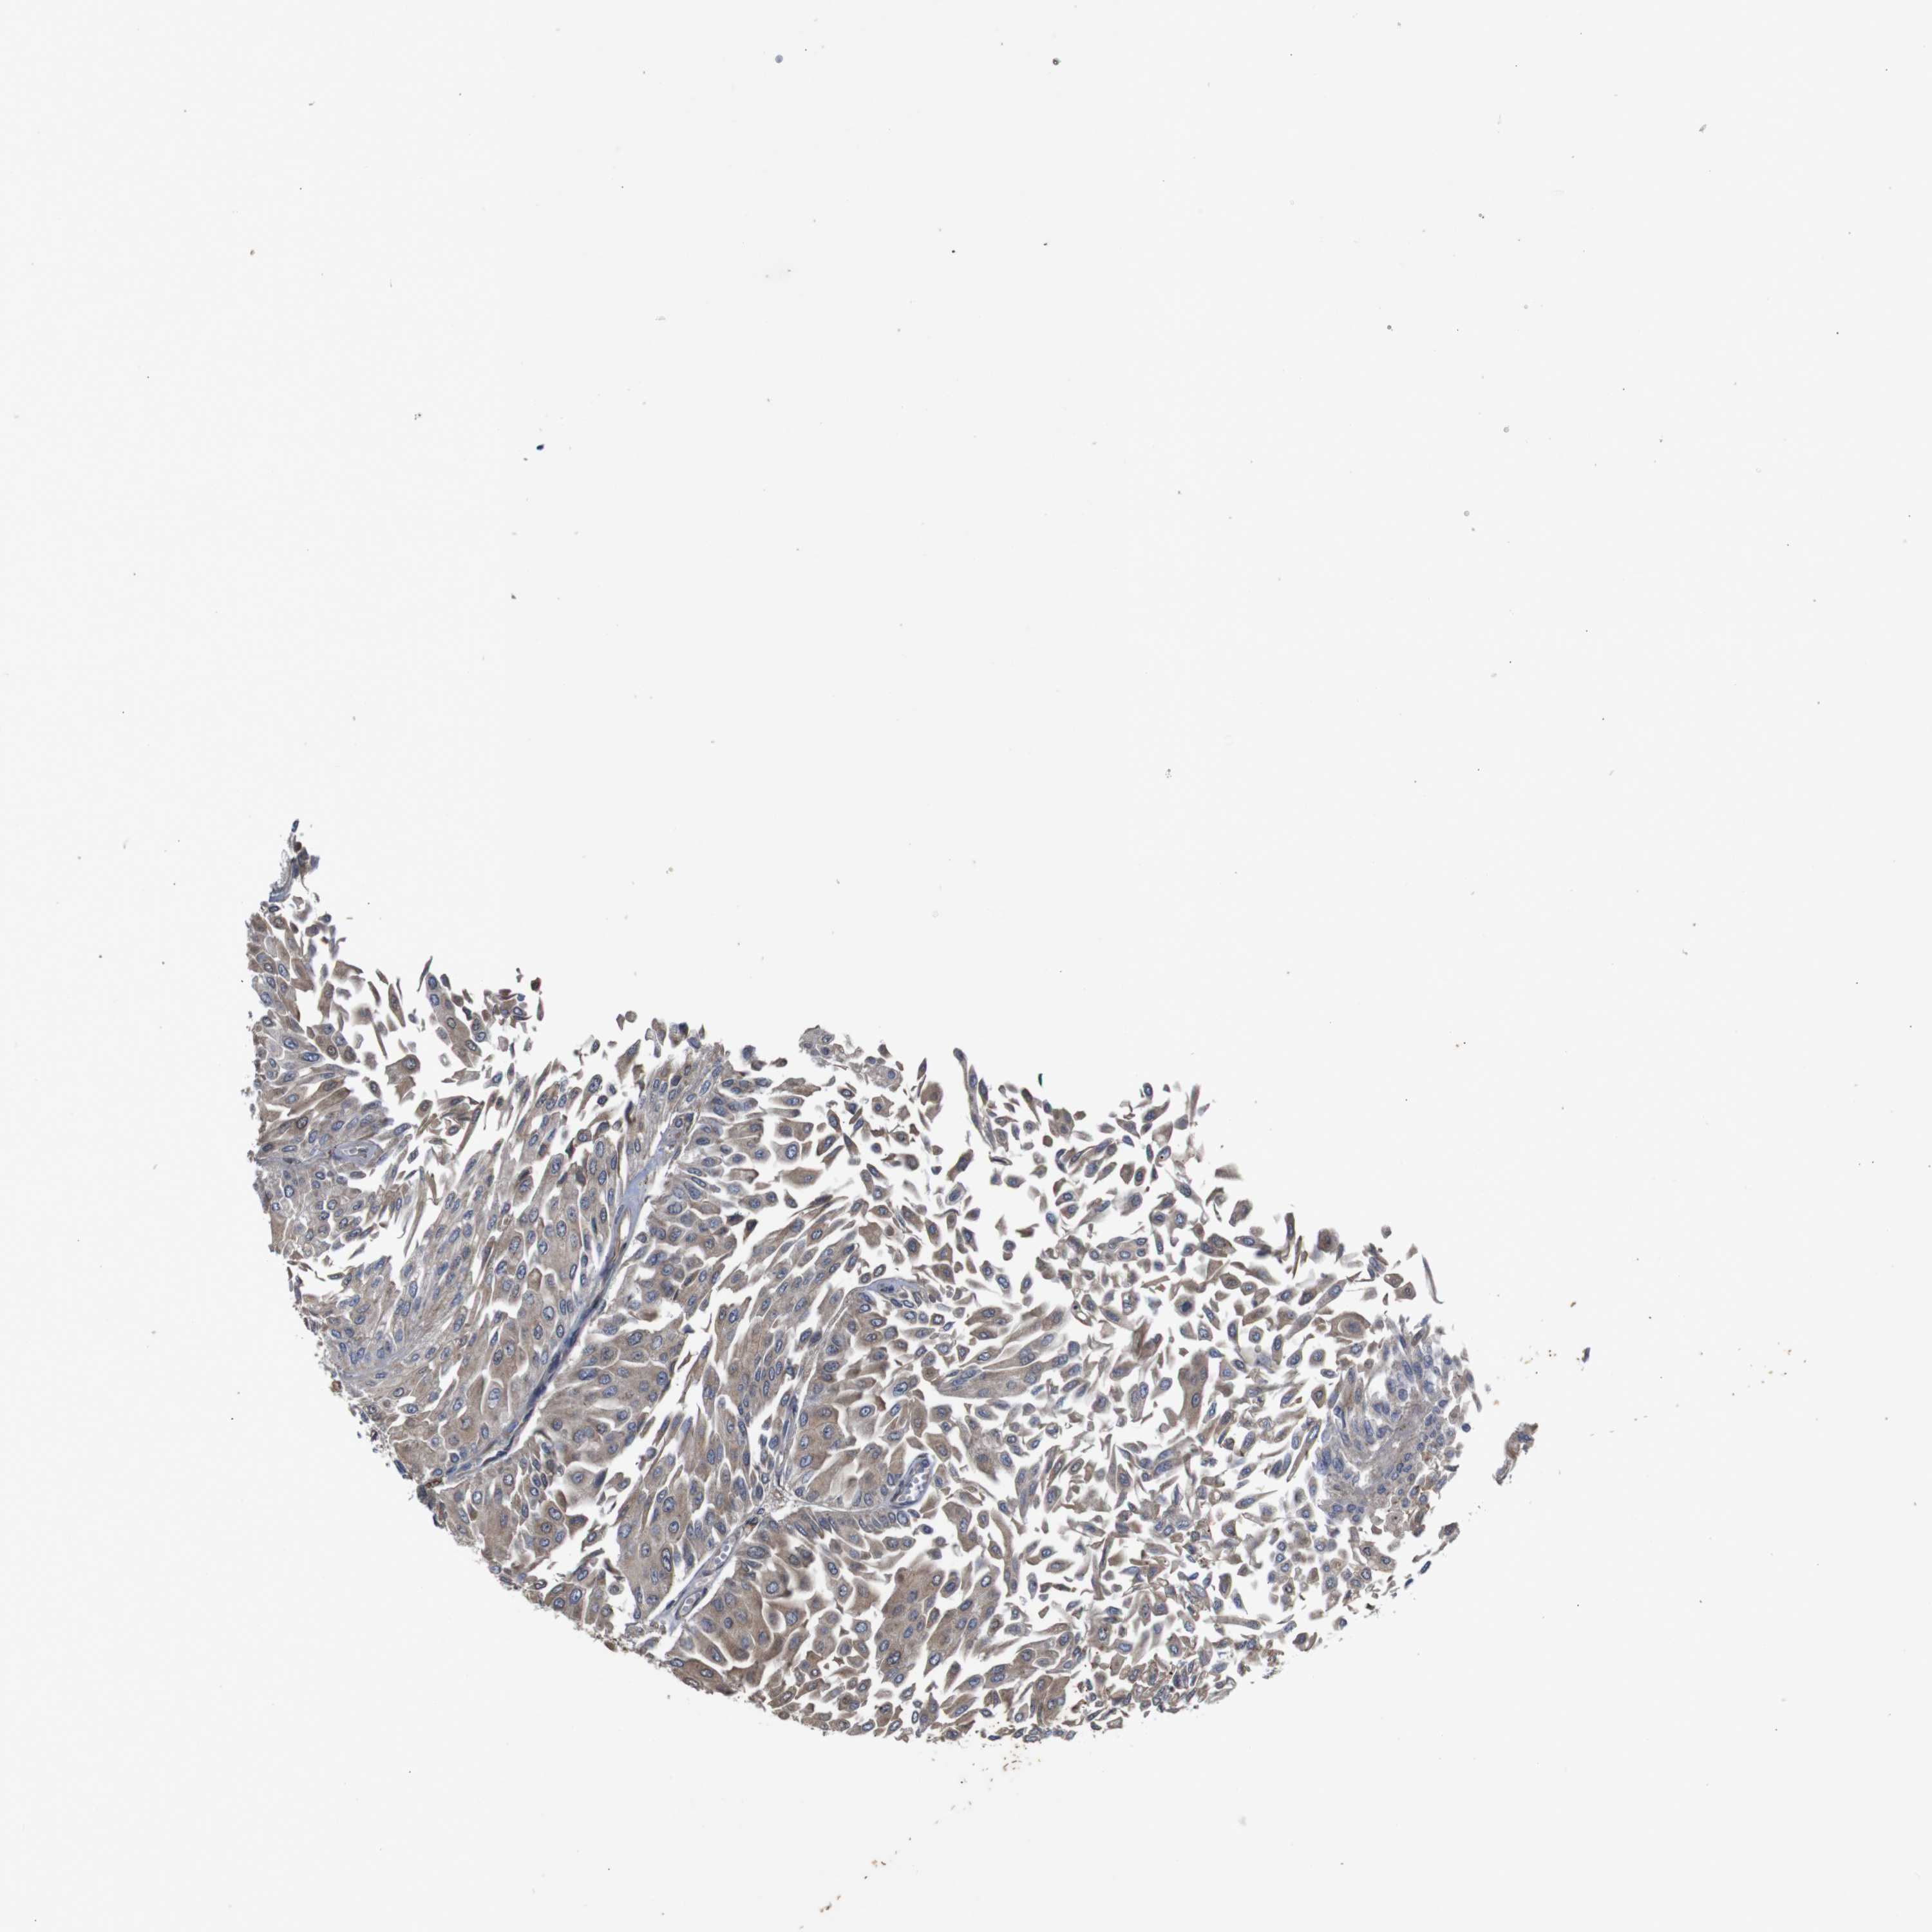

UROTHELIAL CANCER - Protein expressioni

A mouse-over function shows sample information and annotation data. Click on an image to view it in a full screen mode. Samples can be filtered based on level of antibody staining by selecting one or several of the following categories: high, medium, low and not detected. The assay and annotation is described here.

Antibody stainingi

Antibody staining in the annotated cell types in the current human tissue is reported as not detected, low, medium, or high, based on conventional immunohistochemistry profiling in selected tissues. This score is based on the combination of the staining intensity and fraction of stained cells.

Each image is clickable and will lead to virtual microscopy that enables deeper exploration of all samples and also displays staining intensity scores, fraction scores and subcellular localization as well as patient and tissue information for each sample.

Antibody HPA012542

Antibody CAB009329

Antibody CAB015217

Staining

High

Medium

Low

Not detected

Intensity

Strong

Moderate

Weak

Negative

Quantity

>75%

75%-25%

<25%

None

Location

Nuclear

Cytoplasmic/membranous

Cytoplasmic/membranous,nuclear

Urothelial carcinoma, Low grade

Urothelial carcinoma, High grade